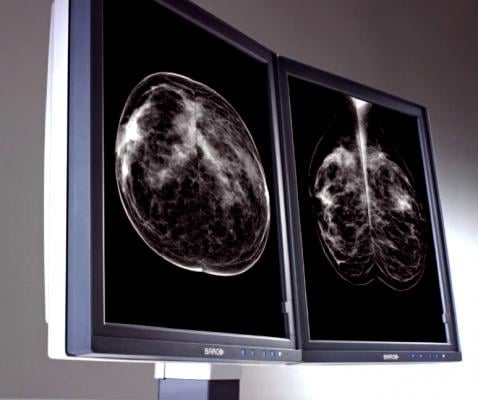

April 26, 2016 — A new study from Elizabeth A. Rafferty, M.D., formerly of Massachusetts General Hospital, and colleagues evaluated the screening performance of digital mammography combined with tomosynthesis compared with digital mammography alone for women with varying levels of breast density. The study appears in the April 26 issue of JAMA.

This study included data from screening performance metrics from 13 U.S. institutions, which were reported for 12 months using digital mammography alone and from the date of introduction of tomosynthesis. Subgroups included the four breast density categories used for clinical reporting. Overall and invasive cancer detection rates and recall rate with and without tomosynthesis were analyzed in patients with both nondense and dense breasts.

Of 452,320 examinations, 278,906 were digital mammography alone and 173,414 digital mammography plus tomosynthesis; 2,157 cancers were diagnosed. The researchers found that the addition of tomosynthesis to digital mammography for screening was associated with a 50 percent increase in cancer detection rate and a 14 percent reduction in recall rate for women with both dense and nondense breast tissue.

“These combined gains were largest for women with heterogeneously dense breasts, potentially addressing limitations in cancer detection seen with digital mammography alone in this group, but were not significant in women with extremely dense breasts,” the authors reported.

They also noted that for women classified as having dense breast tissue, most have heterogeneously dense breasts, mandating caution in drawing conclusions regarding the performance of tomosynthesis for the small proportion of women with extremely dense breasts.